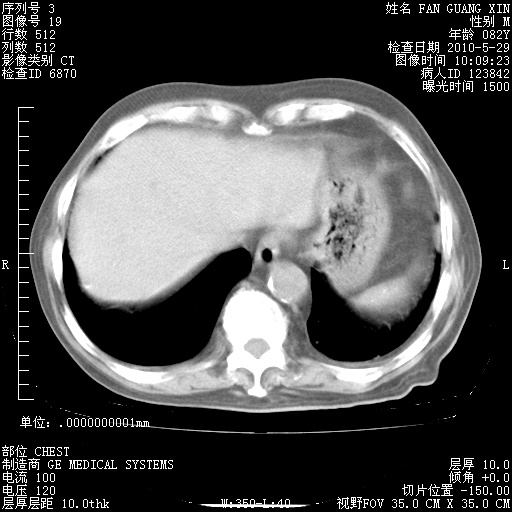

再治疗10天后的肺部CT 纵膈窗

阅读此次胸部CT,肺间质渗出性改变较入院时有吸收。目前从体温、白细胞、中性分叶明显增高,肯定存在细菌感染(发生医院感染哦,若无消化道及泌尿系统等感染的依据,肺部感染可能大)。若你院头孢哌酮舒巴坦钠耐药率较高,同意你的方案,若48小时体温仍高,可考虑使用碳青霉稀类抗菌药物,同时可予超声雾化、注意滴数时加大液体量。白蛋白33.30g/L较低哦,需加强营养等支持治疗。